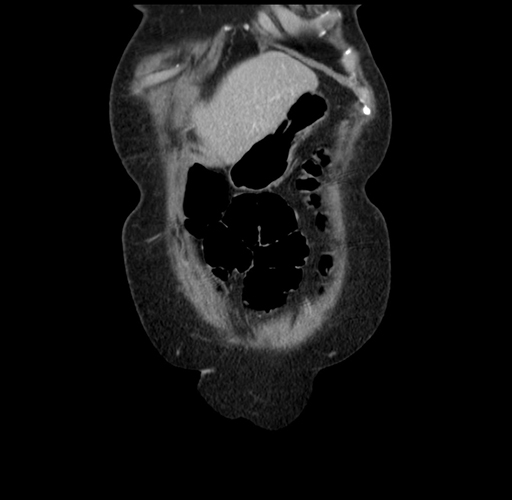

Pre-Chemo: Coronal Venous

Coronal Venous